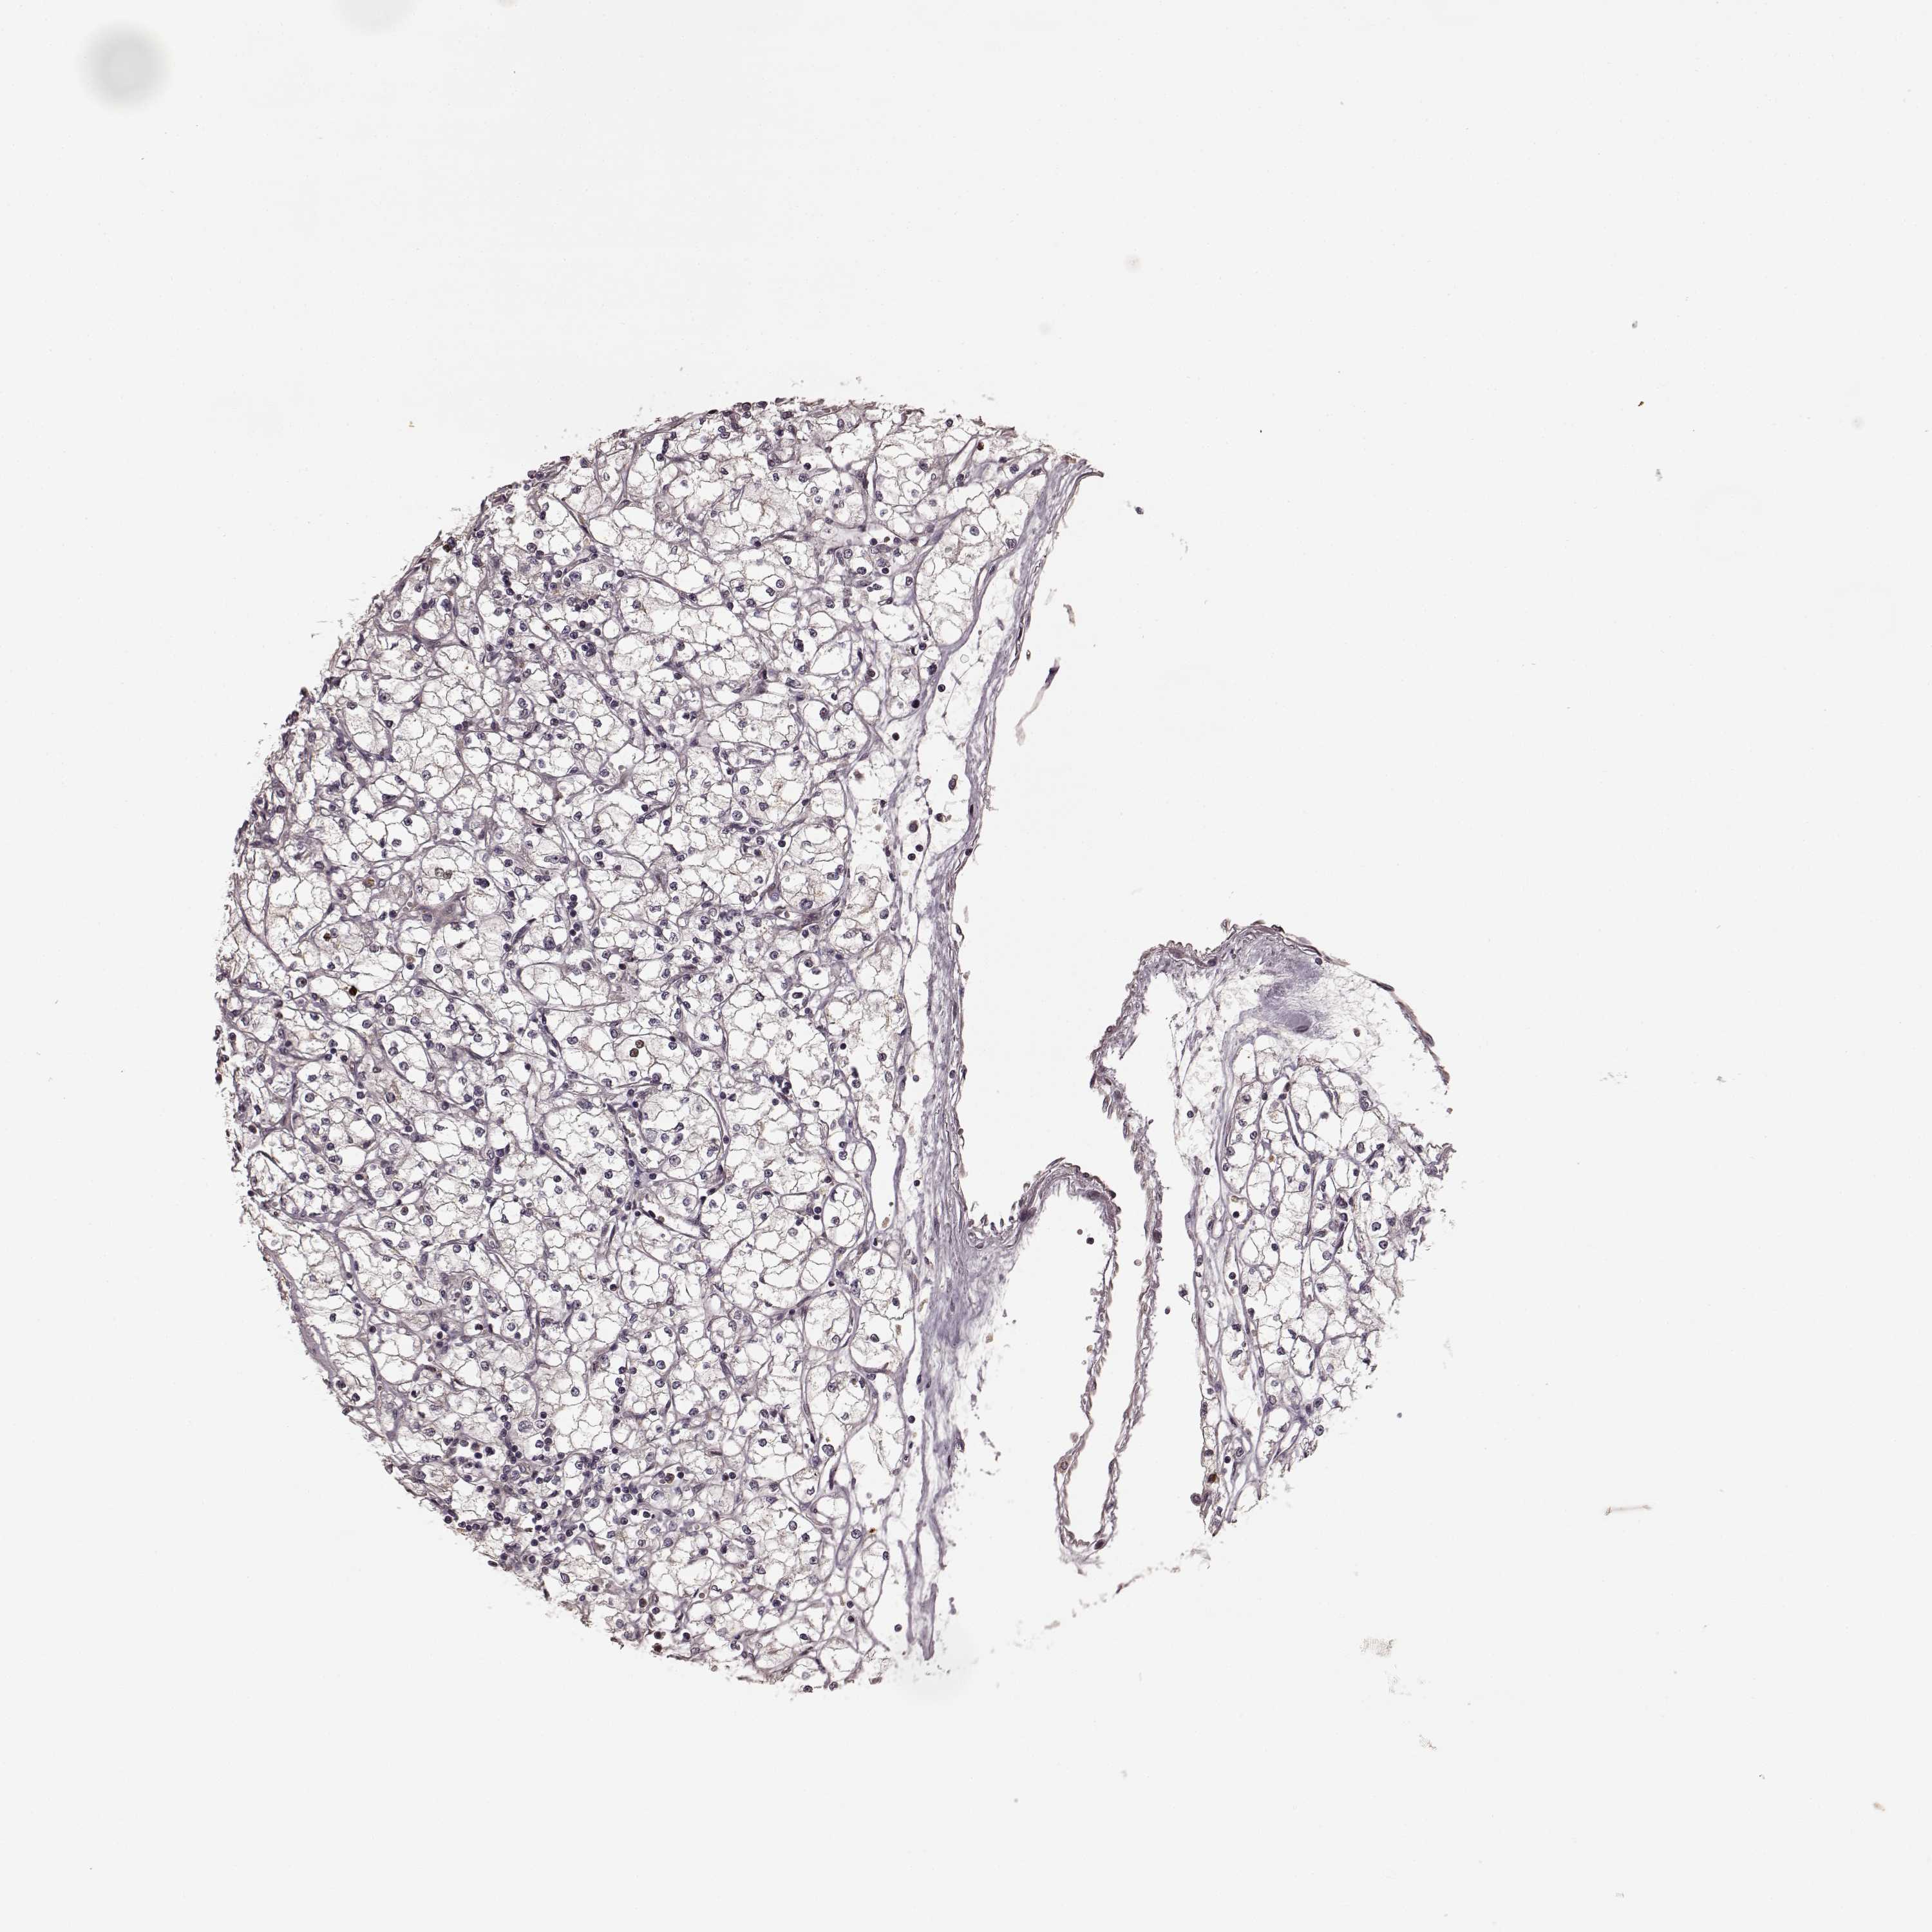

KIDNEY RENAL CLEAR CELL CARCINOMA (VALIDATION) - Interactive survival scatter ploti

The Survival Scatter plot shows the clinical status (i.e. dead or alive) for all individuals in the patient cohort, based on the same data that underlies the corresponding Kaplan-Meier plots. Patients that are alive at last time for follow-up are shown in blue and patients who have died during the study are shown in red.

The x-axis shows the expression levels (FPKM) of the investigated gene in the tumor tissue at the time of diagnosis. The y-axis shows the follow-up time after diagnosis (years). Both axes are complimented with kernel density curves demonstrating the data density over the axes. The top density plot shows the expression levels (FPKM) distribution among dead (red) and alive patients (blue). The right density plot shows the data density of the survived years of dead patients with high and low expression levels respectively, stratified using the cutoff indicated by the vertical dashed line through the Survival Scatter plot. This cutoff is automatically defined based on the FPKM cutoff that minimizes the p-score. The cutoff can be changed by dragging the vertical line or by entering a cutoff value in the square labeled "Current cut-off".

Under the Survival Scatter plot the p-score landscape (black curve; left axis) is shown together with dead median separation (red curve; right axis). Dead median separation is the difference in median mRNA expression between patients who have died with high and low expression, respectively. It is calculated as follows: median FPKM expression of dead patients with high expression - median FPKM expression of dead patients with low expression. This is intended to aid the user in visually exploring custom cutoffs and the associated p-scores and dead median separation.

Individual patient data is displayed and can be filtered by clicking on one or more of the category buttons on the top of the page. Categories describing expression level and patient information include: high, low, alive, dead, female, male and tumor stages. The scale of the x-axis can be toggled between linear and log-scale by clicking on the "x log" button. Mouse-over function shows TCGA ID, patient information and mRNA expression (FPKM) for each patient.

& Survival analysisi

Kaplan-Meier plots summarize results from analysis of correlation between mRNA expression level and patient survival. Patients were divided based on level of expression into one of the two groups "low" (under cut off) or "high" (over cut off). X-axis shows time for survival (years) and y-axis shows the probability of survival, where 1.0 corresponds to 100 percent.

SLC12A9 is not prognostic in Kidney Renal Clear Cell Carcinoma (validation)

Best expression cut offi

Based on the FPKM value of each gene, patients were classified into two groups and association between prognosis (survival) and gene expression (FPKM) was examined. The best expression cut-off refers the FPKM value that yields maximal difference with regard to survival between the two groups at the lowest log-rank P-value. Best expression cut-off was selected based on survival analysis .

When clicking on this number, the vertical dashed line indicating cut-off, the interactive survival plot, and the Kaplan-Meier curve will be adjusted to show results based on the best expression cut-off.

: 18.63

TCGA RNA samplesi

RNA-seq data is reported as average FPKM (number Fragments Per Kilobase of exon per Million reads), generated by the The Cancer Genome Atlas (TCGA) .

Normal distribution across the dataset is visualized with box plots, shown as median and 25th and 75th percentiles. Points are displayed as outliers if they are above or below 1.5 times the interquartile range. FPKM values of the individual samples are presented next to the box plot.

Average pTPM 16.2

Number of samples 100